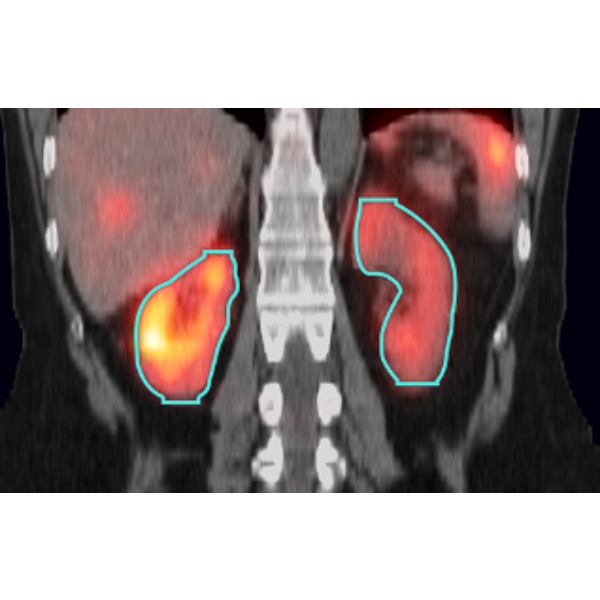

MIM SurePlan MRT's automated segmentation can significantly reduce the time required to generate organ volumes including the liver and kidneys. Industry-leading PET and segmentation tools are also available for tumors and other volumes of interest.